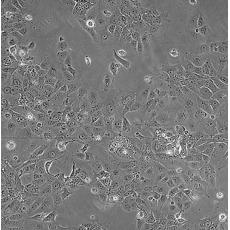

HCC827

中文名稱 人非小細胞肺癌細胞

組織來源 肺腺癌;女性

生長特性 adherent

形態(tài)特征 epithelial

細胞描述 This lung adenocarcinoma has an acquired mutation in the EGFR tyrosine kinase domain(E746-A750 deletion).